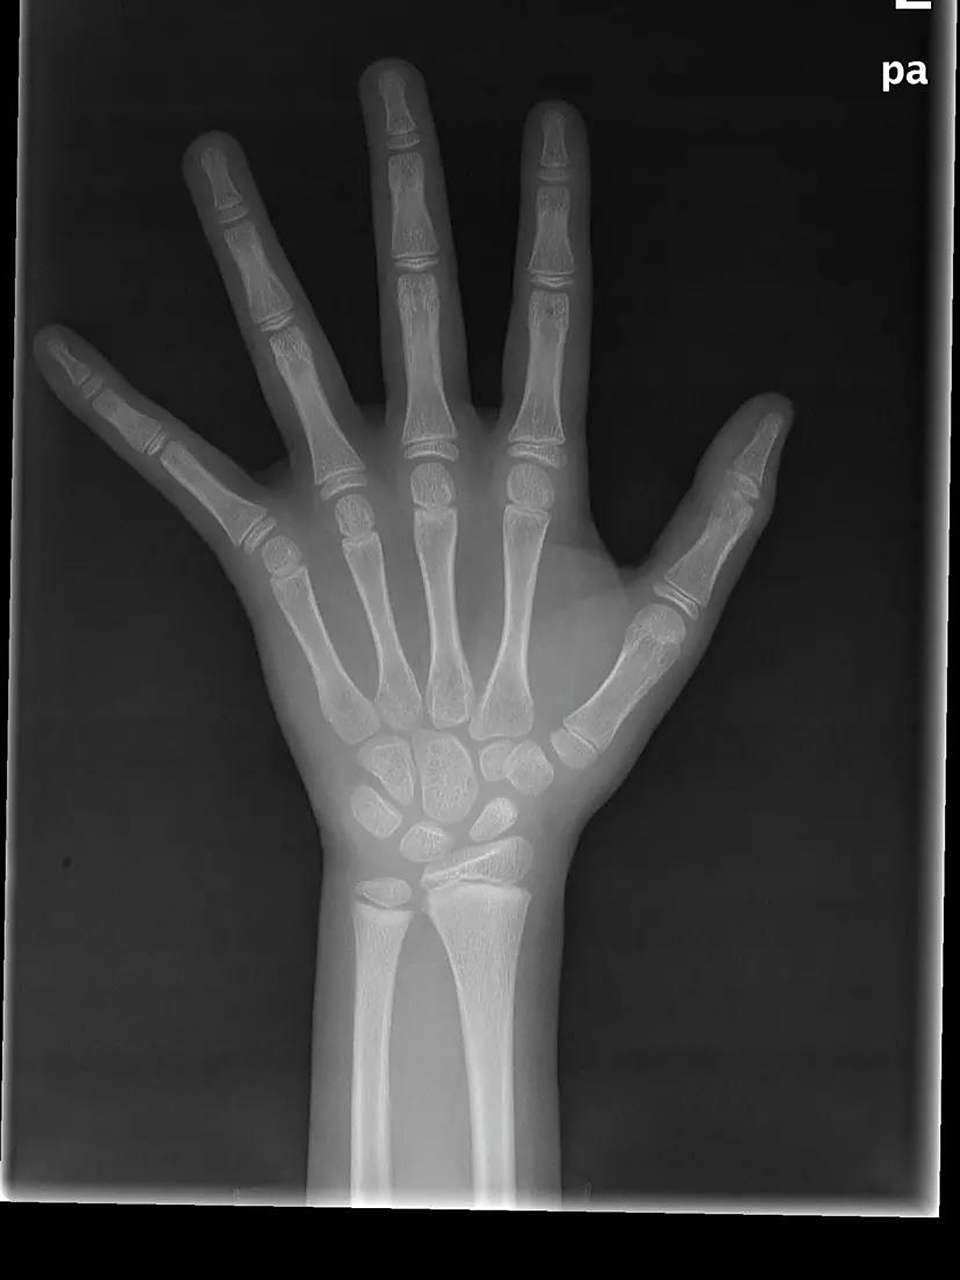

骨龄片

帮忙看看这个骨龄片,12周岁六个月的男孩子,骨龄片上显示骨龄多少岁?